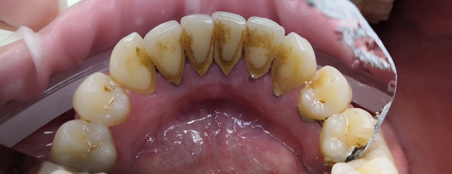

Наши работы

пародонтологов в КосмоСтом

Главная причина поражения десен – недостаточная забота о чистоте полости рта. Правильная паста, зубная нить, регулярная профессиональная чистка зубов у стоматолога – залог здоровья пародонта. Пренебрежение правилами гигиены приводит к тому, что болезнетворные организмы, размножающиеся в зубном налете, для начала вызывают неприятный запах – первый сигнал о том, что со здоровьем зубов и десен что-то не то. Если будущий пациент стоматолога не примет меры и не начнет регулярно чистить и зубы, и десны, болезнь прогрессирует: десны воспалятся и начнут кровоточить. Такое воспаление, или гингивит, легко переходит в следующую стадию –пародонтит, избавиться от которого намного труднее. В результате зуб держится в десне не так прочно и даже может выпасть.

Как происходит разрушение связей между деснами и зубами? При заболеваниях парадонта страдают микроскопические связочные волокна, которые удерживают зуб в челюстной кости. В начале болезни волокна воспаляются, а затем рвутся и безвозвратно погибают. Между зубом и десной появляются патологические зубодесневые карманы, в которых скапливаются бактерии. Процесс развивается медленно, но в одном направлении: все идет к разрушению костной ткани, которая окружает корни зубов. Если даже на этом этапе больной не спохватится, обращаться ему придется в дальнейшем не к пародонтологу, а к протезисту, стоимость услуг которого на порядок выше, чем затраты на лечение десен.

Какие симптомы должны заставить больного насторожиться? Прежде всего, это кровоточивость десен при любых механических движениях, неприятный запах, повышенная чувствительность зуба к раздражителям, боль, появляющаяся при жевании и исчезающая в состоянии покоя. С этими признаками нужно немедленно отправляться к врачу, чтобы пройти диагностику и получить правильное лечение. Покрасневшие или кровоточащие во время чистки зубов десны – верный признак, что к пародонтологу нужно отправляться немедленно. Однако лучше предупредить проблему, помня о статистике: шансы оказаться в числе 85 %, имеющих проблемы с деснами, очень велики.